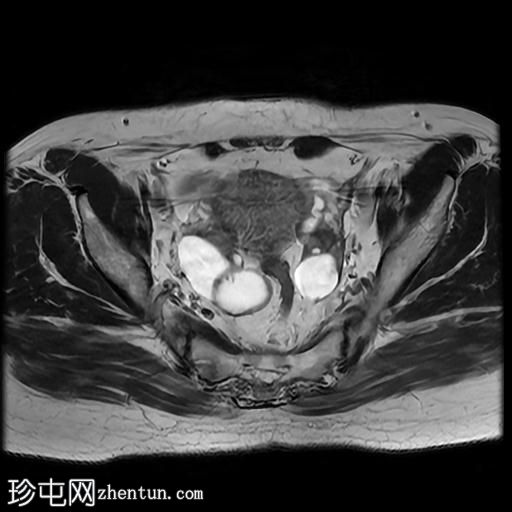

轴位

T2加权像

右侧输卵管呈管状囊性扩张,直径达30 mm,提示输卵管积水,呈均匀液体信号,无实性成分。

左侧输卵管亦有轻度扩张,直径26 mm,符合输卵管积水表现。

右侧卵巢可见一单纯性卵巢囊肿,大小约35 x 40 mm,呈正常液体等效信号。

宫内节育器位置正常。

MRI 检查结果显示双侧输卵管积水和右侧卵巢单纯性囊肿。总体而言,所有附件和盆腔检查结果均显示良性 MRI 特征(O-RADS 2 类),无恶性肿瘤迹象。